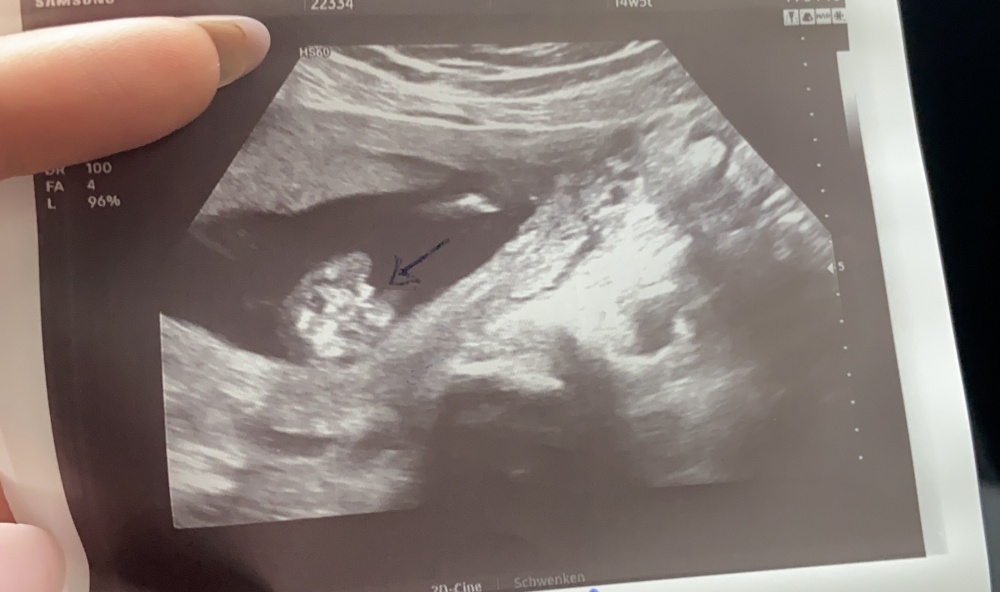

Das Bild ist von der 14 ssw.